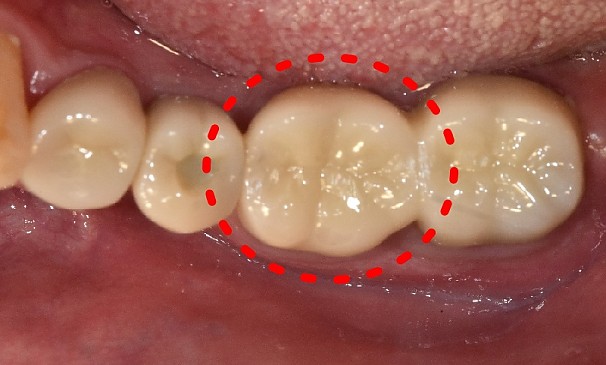

노OO님 전후사진 | 치료 기간 : 1주

치료 전

치료 후

+